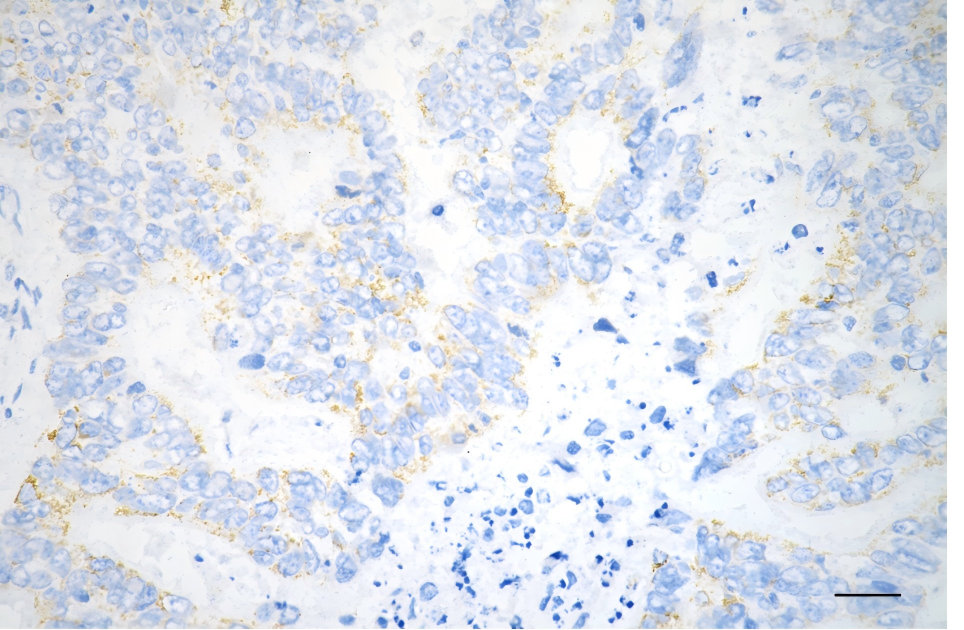

Immunohistochemistry was performed on paraffin-embedded human sigmoid colon carcinoma using glutaminase antibody. Antigen retrieval was done in sodium citrate buffer (pH 6.0). DAB was used for detection, with hematoxylin counterstaining. Images were acquired using a Nikon Ci-L Plus microscope (40× objective). Scale bar: 25 μm.